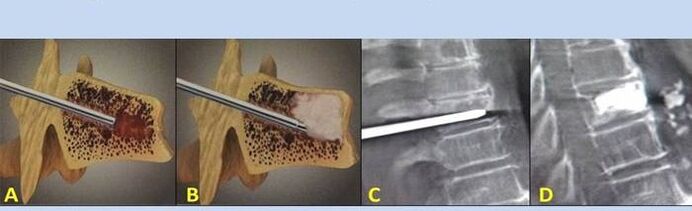

- Nukleoplastyka – usunięcie rdzenia krążka międzykręgowego. Operacja zmniejsza nacisk na zakończenia nerwowe.

- Wertebroplastyka punkcyjna – sposób stabilizacji kręgów. Podczas zabiegu lekarz wypełnia ubytki kręgosłupa cementem kostnym.